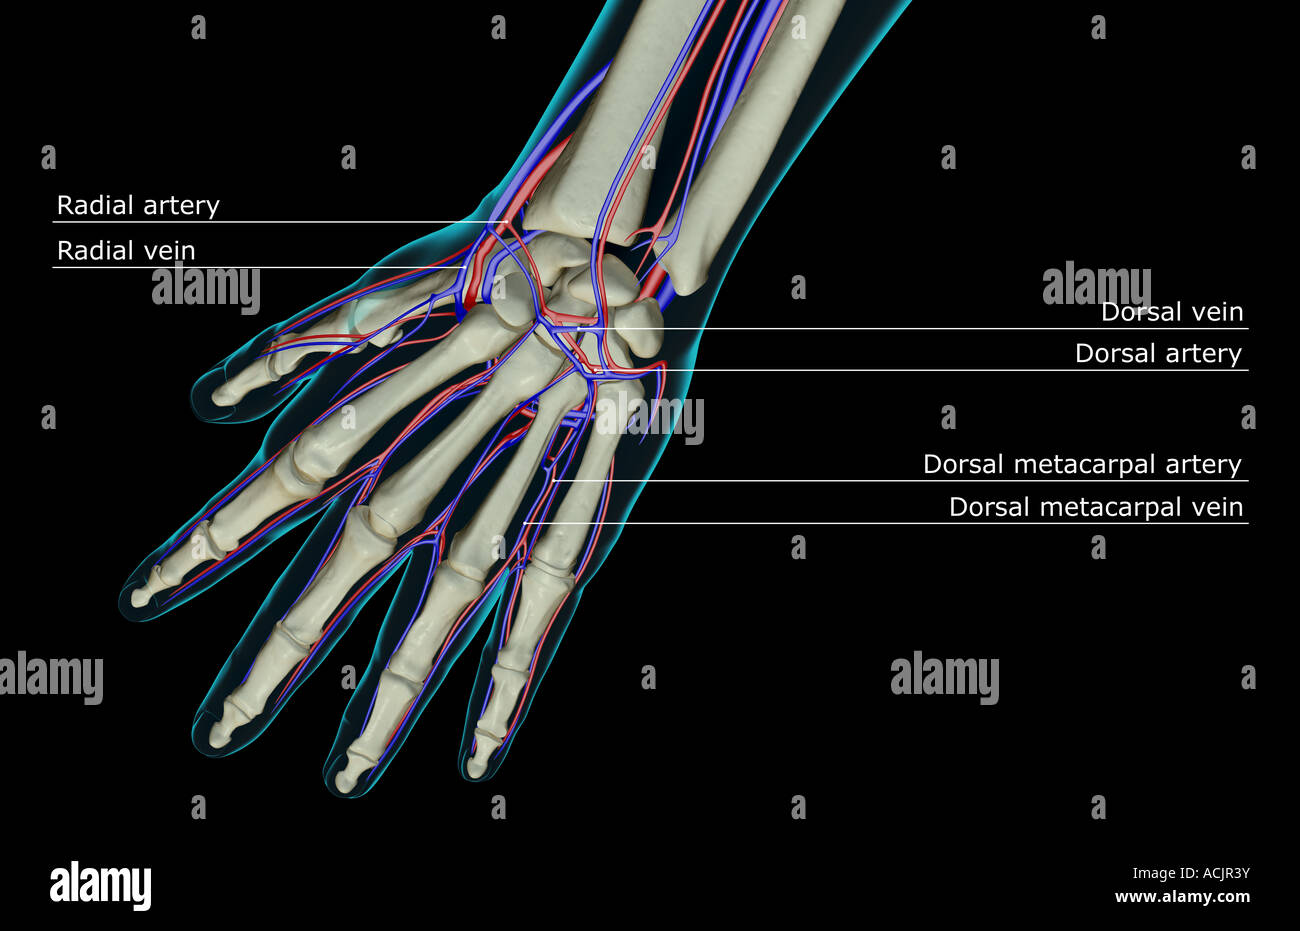

The blood supply of the hand Stock Photohttps://www.alamy.com/image-license-details/?v=1https://www.alamy.com/stock-photo-the-blood-supply-of-the-hand-13172702.html

The blood supply of the hand Stock Photohttps://www.alamy.com/image-license-details/?v=1https://www.alamy.com/stock-photo-the-blood-supply-of-the-hand-13172702.htmlRFACJR3Y–The blood supply of the hand